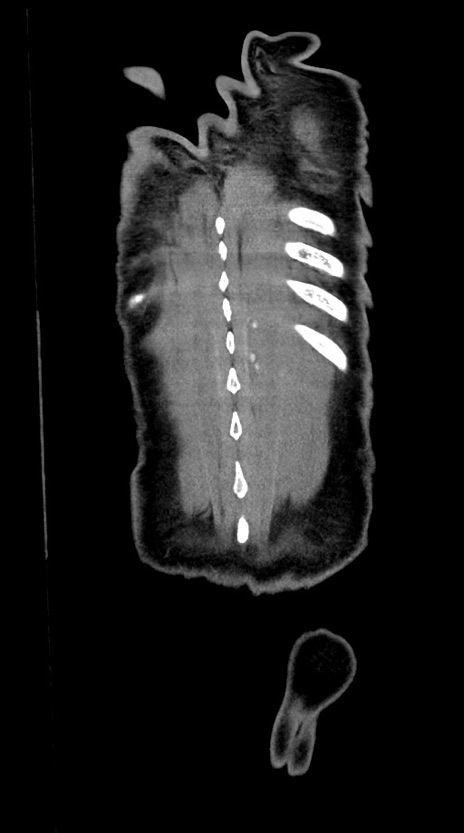

横断像

【症例】60歳代男性

【主訴】嘔吐

【現病歴】胃癌にて胃全摘後。食思不振が悪化し、夜中に嘔吐することがある。

【既往歴】胃癌、胃全摘、脾摘、胆摘後

【データ】WBC 5900、CRP 10.56